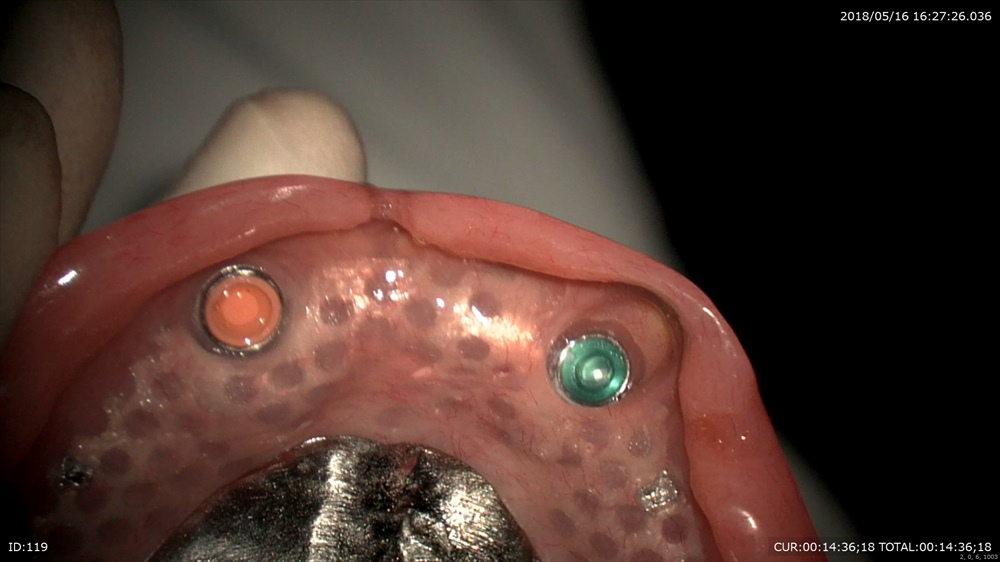

入れ歯のケース

自分の歯1本と1本インプラントを利用して

上の入れ歯の治療。

いままでは、このように上顎に全部、床がきて食事がおいしくない。

裏側にこの様な器具でくりぬけます。

今日から食事の味が変わります!!